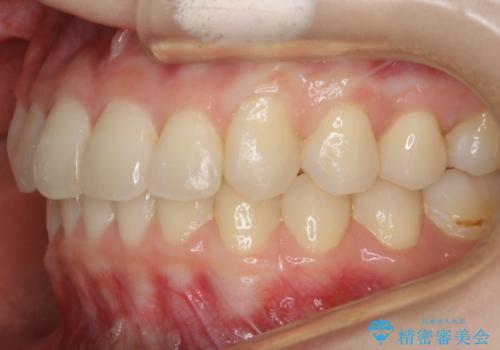

- 笑った時の歯の見え方を治したいとのことで矯正相談にいらっしゃいました。

一見そこまで大きなガタつきはないようにも見えますが、前歯の角度の不揃いや噛み合わせのズレなどから見え方に影響が出てしまっていました。

抜歯は全く必要のないレベルのガタつきだったため、マイクロインプラントを用いて歯全体を後方に移動させていくことできれいな歯並びを獲得することができました。